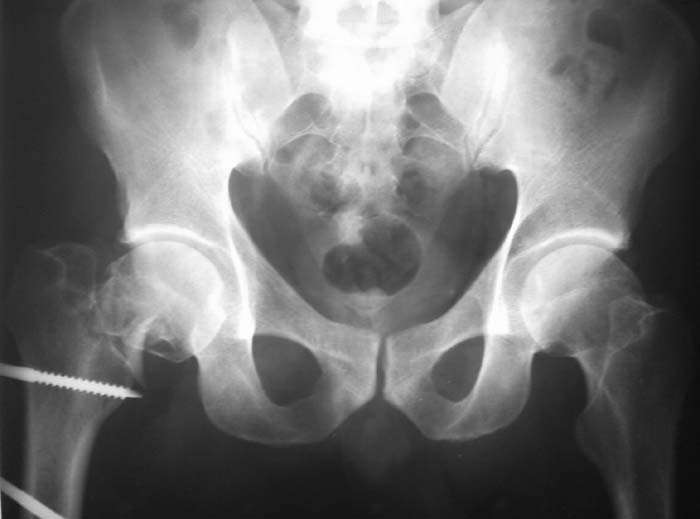

Мужчина, 44 г. Травма в ДТП 22.08.08: открытый перелом ср\3 диафиза правой бедренной кости, закрытый оскольчатый перелом правого локтевого отростка со смещением, в\3 правой лучевой кости со смещением, закрытый перелом верхушки внутренней лодыжки правой голени.

Находился на лечении в одной из городских больниц (где в ургентном порядке произведена операция - ПХО ран, ЧКО правого бедра аппаратом спице-стержневого типа, иммобилизация правого предплечья гипсовой повязкой). Переведен для дальнейшего лечения в ДНИИТО. Через 18 дней после травмы выполнены рентгенограммы таза - диагностирован перелом шейки бедра. На данный момент раны бедра заживают вторично с участками некроза.

Male, 44 y.o. Trauma in MVA 22.08.08: open fracture of right femur (middle shaft), close fractures of right elbow and pilon.

He was in rural hospital were debridgement and Ilizarov frame for femur were performed. Now, he is in Regional Trauma Hospital. After 18 days of trauma x-ray of pelvis were performed – fracture of right femur neck. Wounds at femur is healing with small points of necrosis.

Hi! In this case we can see complecated fracture femoral neck, I think subcapital with comminution to midcervical area.About fracture shaft femur this very easy- intramedullary interlokking nail

Becouse very complecated case may be need open reduction of neck fracture. Very critically to explain to patient about very higt percent AVN femoral head in this type fracture.